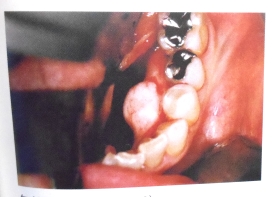

術中の口腔内写真を別に示す

下顎隆起の除去に用いるのはどれか

2つ選べ

a 剪 刃

b 挺 子

c 骨ノミ

d マレット